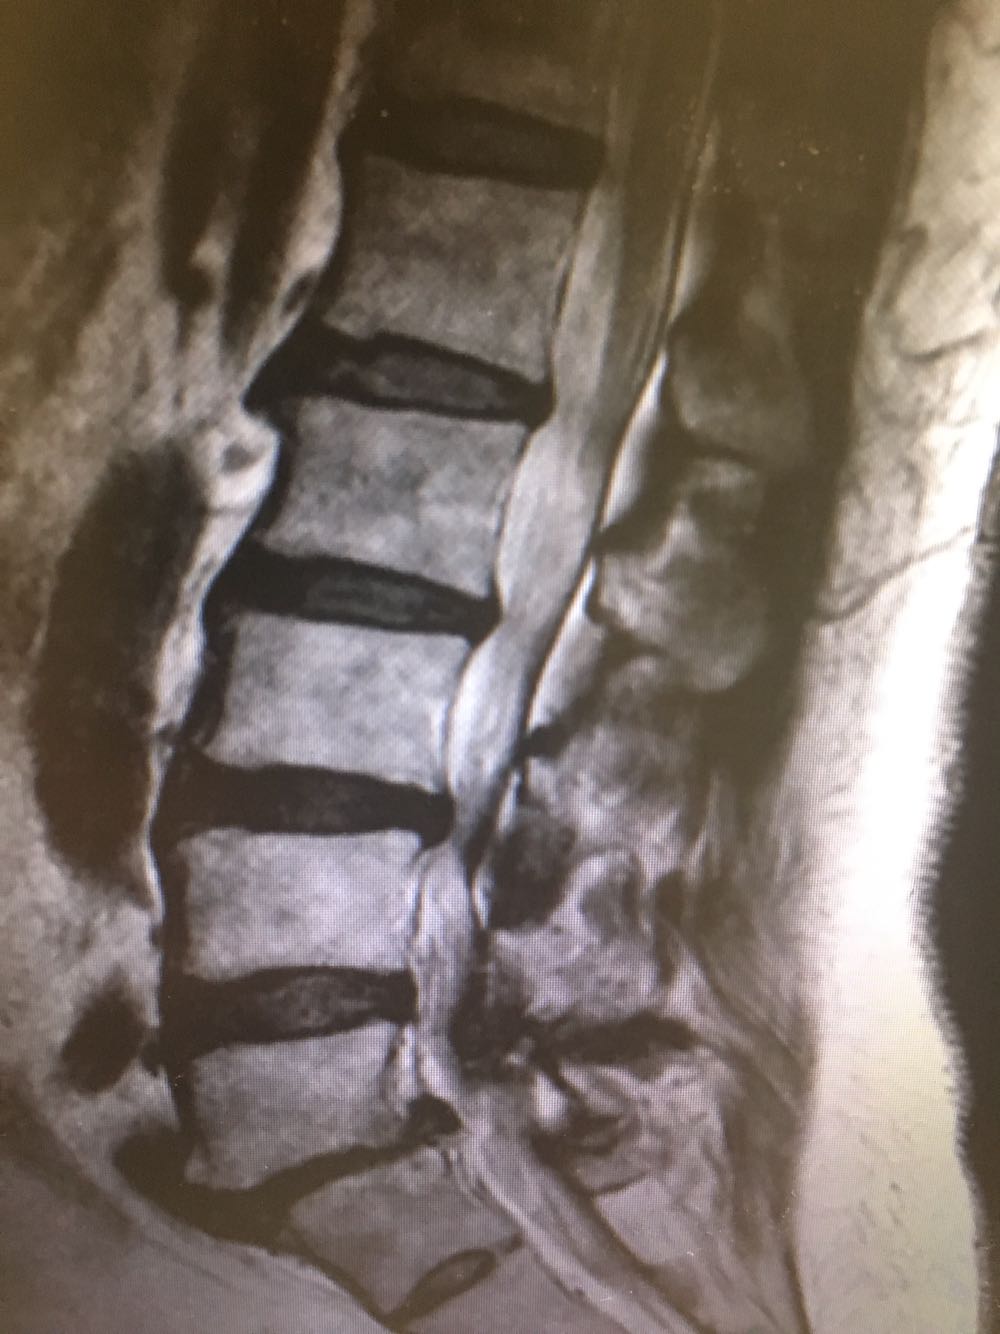

患者,女性,60岁 主诉:腰痛伴下肢疼痛2年 现病史:患者于2年前无明显诱因下出现腰痛伴左侧下肢疼痛,休息后缓解,未予重视,半年前出现双下肢外侧疼痛,酸胀伴跛行,休息后稍缓解,病程中否认头晕头痛、恶心呕吐等不适,遂至我院门诊就诊,查腰椎X片示:L5椎体向前轻度滑脱,伴退行性变,椎间隙变窄,现为进一步诊治收治入院,发病以来,神清,精神可,胃纳夜眠可,二便无殊,体重无明显变化。

查体:脊柱无侧弯畸形,下肢肌力肌张力正常,下肢反射均正常。 辅检:腰椎MRI